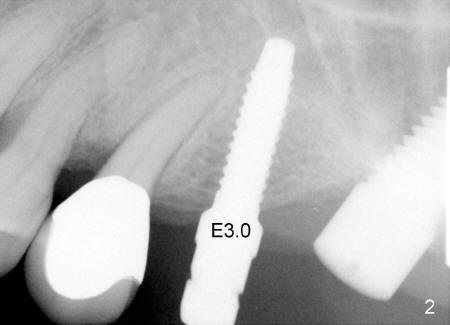

When RT2, bone expanders 2.6, 3.0 (Fig.2) were used, they were intentionally oriented parallel to the the crown axis of the tooth #13. The X-ray shows that the tip of the bone expander 3.0 is too close to the tip of #13 root.